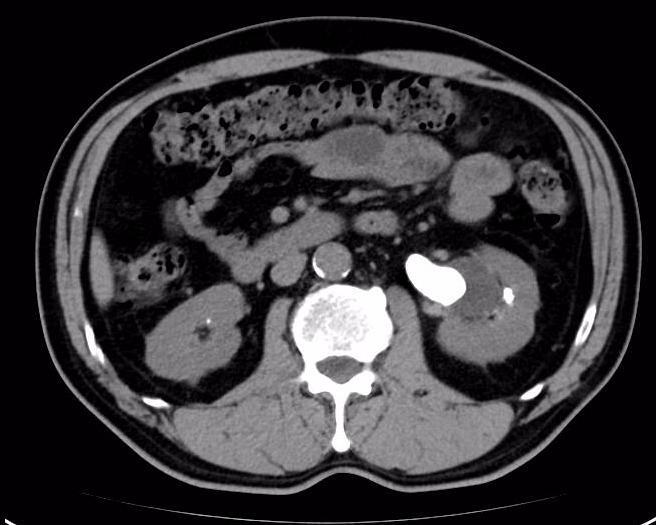

图片4.jpg

术后3周左肾结石已经消失

完善相关检查后,积极做好术前准备在手术室全麻下行左输尿管软镜下肾碎石取石。我们采用输尿管软镜下碎块法联合快速套石法处理巨大结石(直径>3cm)获得良好的效果。该病例所示术后第一天肾区所见结石粉末化。术后3周复查KUB提示“原左肾结石已经消失,左侧输尿管支架管位置良好”。